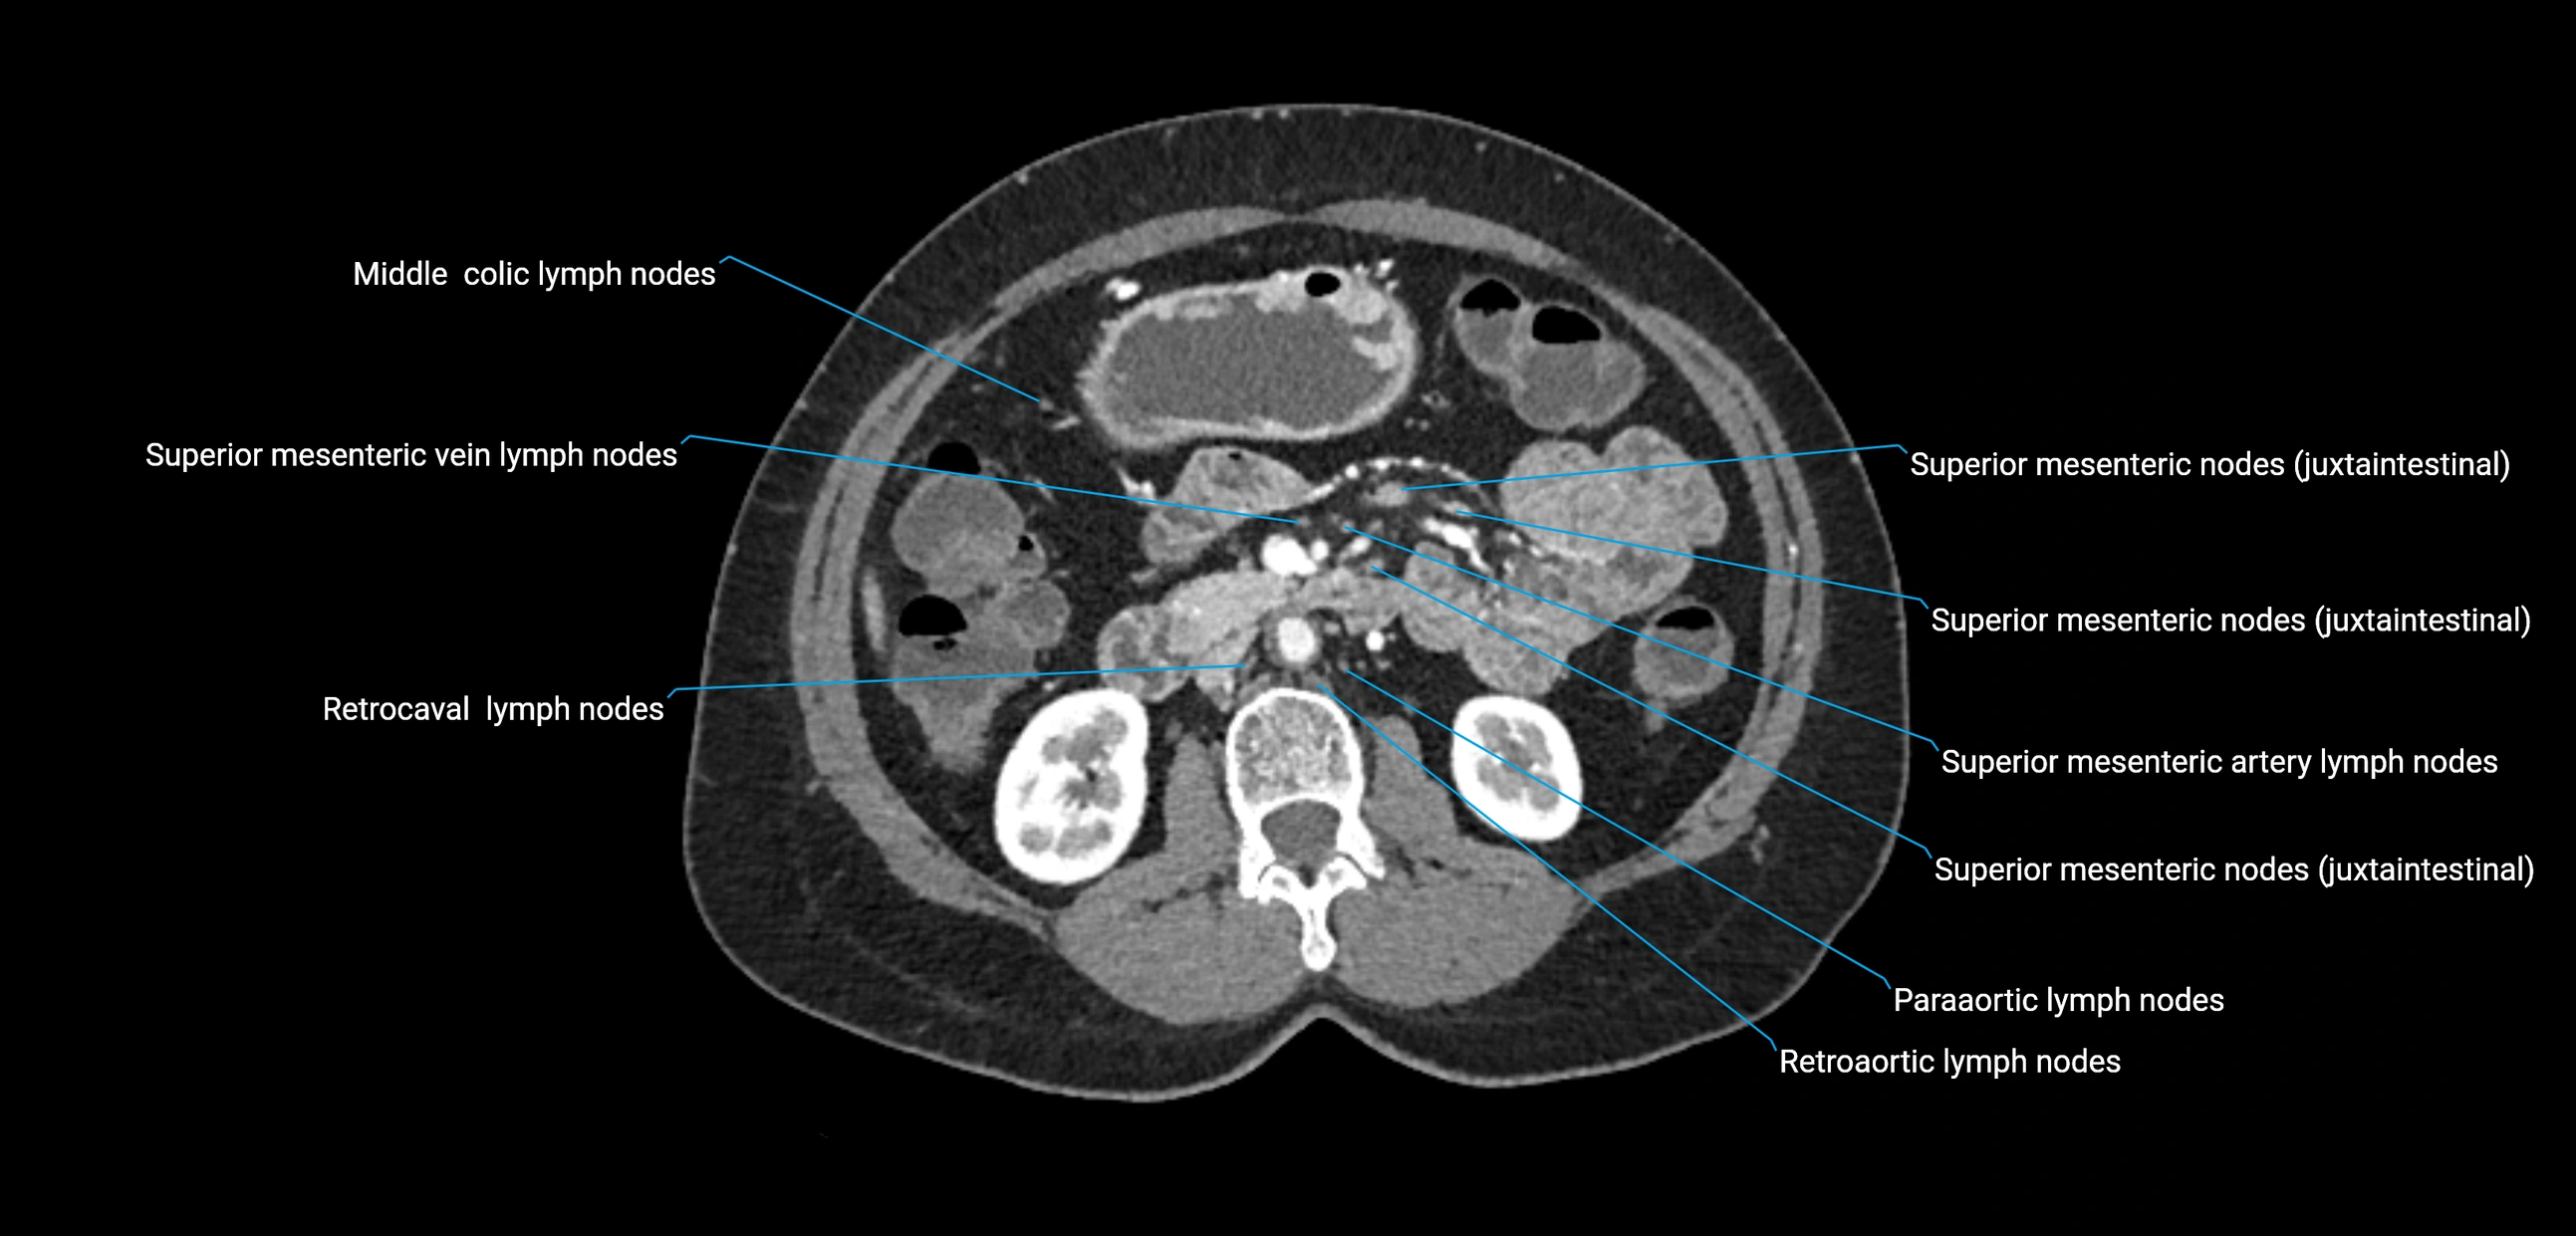

CT Appearance

CT Pre-Contrast:

• Nodes appear as soft-tissue density nodules adjacent to the aorta and IVC

• Calcification may be seen in chronic infections (e.g., tuberculosis)

CT Post-Contrast:

• Normal nodes enhance homogeneously

• Malignant nodes may show heterogeneous enhancement, central necrosis, or conglomerate formation

• Size >1 cm short axis is suspicious, though morphology and distribution are equally important

CT Venography (CTV):

• Demonstrates nodal encasement or compression of adjacent vessels (aorta, IVC, renal veins)

• Useful in staging testicular and ovarian malignancies

• Provides 3D reconstructions for retroperitoneal lymph node dissection planning

CT image

image